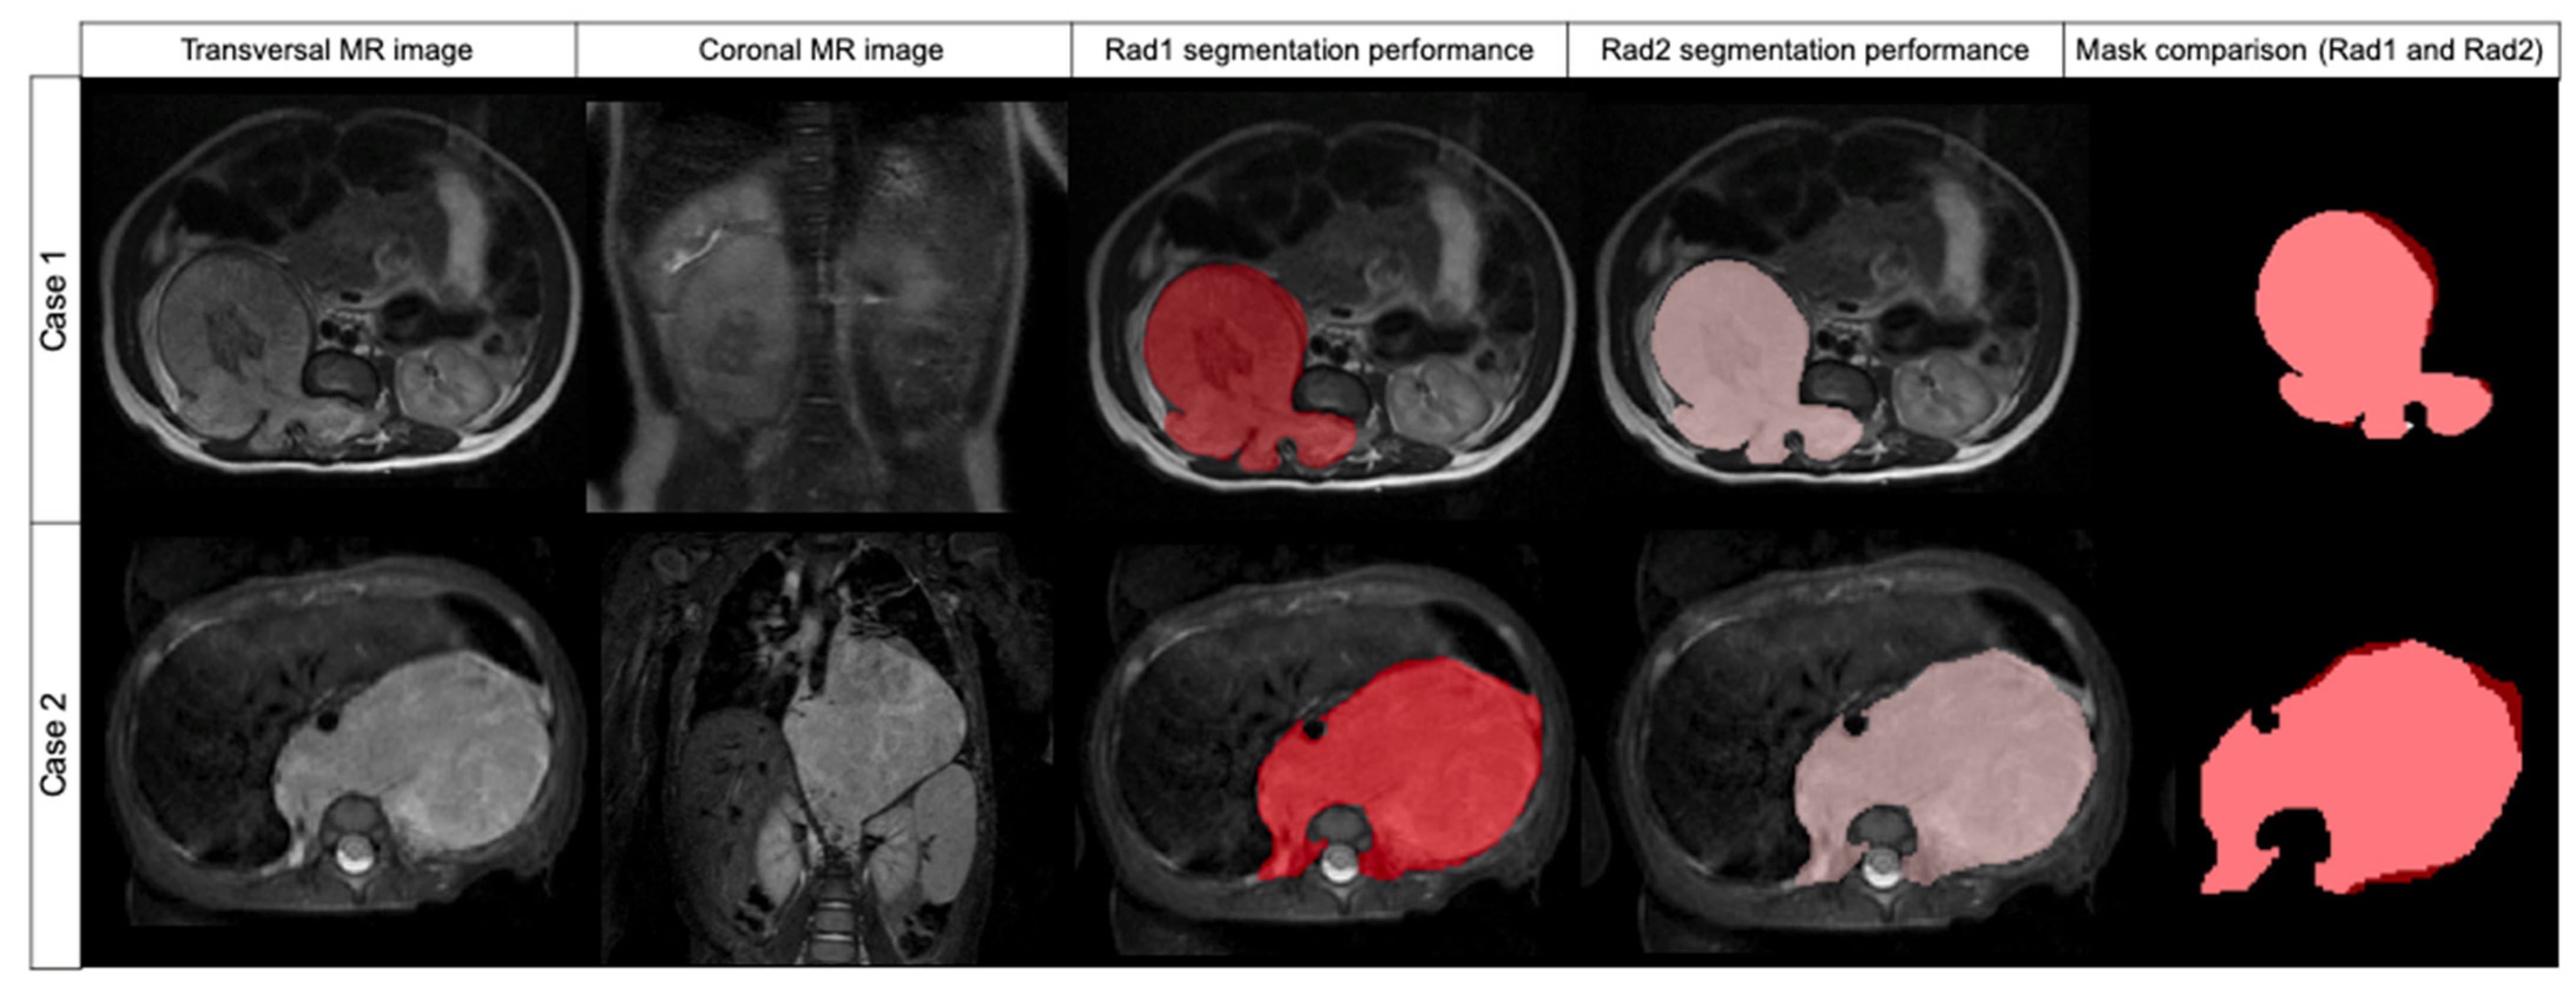

Figure 3. Comparison of two cases segmented by Radiologist 1 (red label) and Radiologist 2 (pink label) and mask superposition and comparison. Case 1 was segmented in T2w while case 2 was segmented in T2w fat-sat. In both cases, DSC was 0.957.